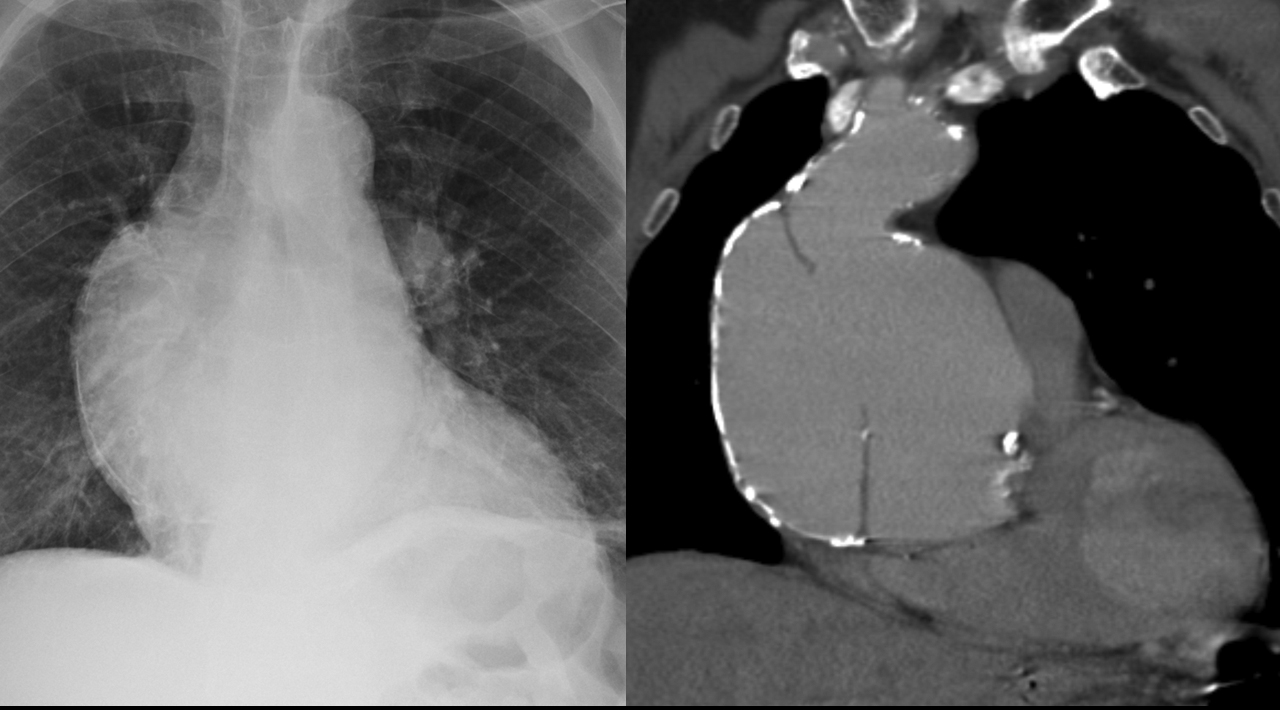

Gallery Cardiac Other Aortic aneurysm

Aortic aneurysm